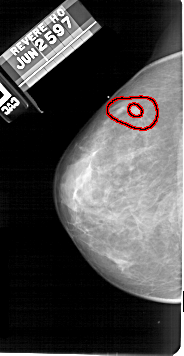

A_1673_1.RIGHT_MLO

RIGHT_MLO LINES 5491 PIXELS_PER_LINE 2761 BITS_PER_PIXEL 12 RESOLUTION 43.5 NON_OVERLAY

FILE: A_1673_1.LEFT_MLO.OVERLAY

TOTAL_ABNORMALITIES 1

ABNORMALITY 1

LESION_TYPE MASS SHAPE IRREGULAR MARGINS SPICULATED

ASSESSMENT 5

SUBTLETY 4

PATHOLOGY MALIGNANT

TOTAL_OUTLINES 2